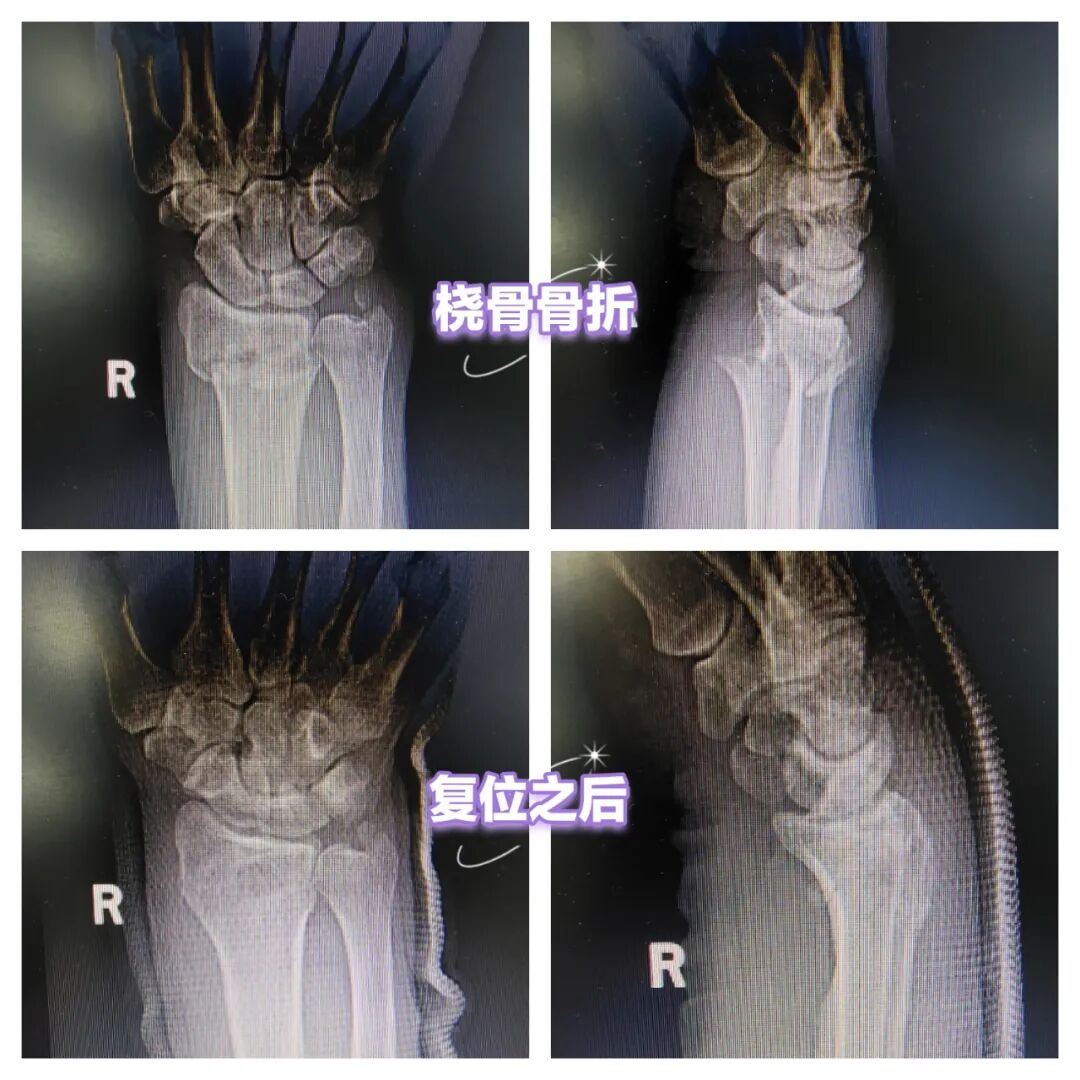

王先生原本是开车上班,因为想欣赏雪后景色、呼吸呼吸新鲜空气,临时改为步行上班,没想到摔了一跤,撑在地面的右手传来一阵疼痛,在家属的陪同下,来到长治二院急诊医学科就诊,张晓波医生查体腕部呈“餐叉样”畸形,X线显示为桡骨远端骨折。张医生和家属沟通了病情与治疗方案之后,在局部麻醉下对患者进行了骨折手法复位。